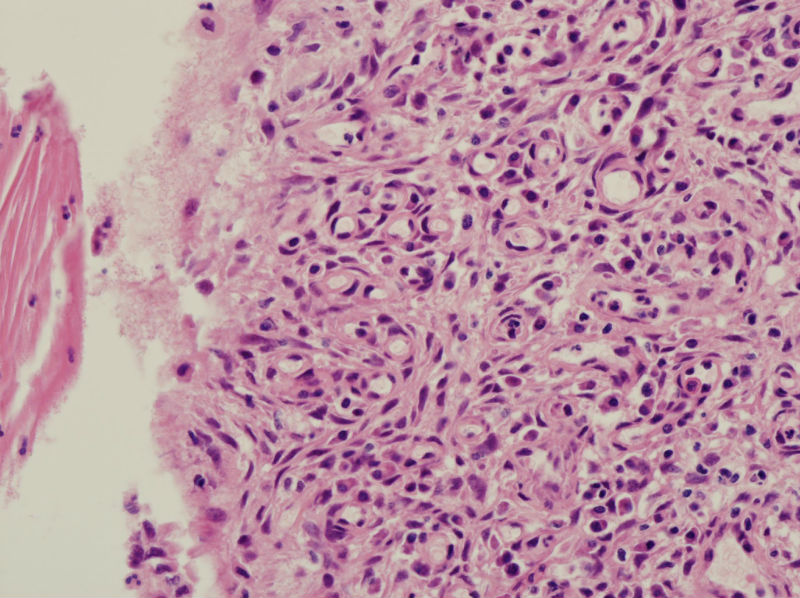

45岁,宫颈息肉?请老师指教

• 45岁,宫颈息肉?请老师指教图1

图1

慢性炎,腺体有鳞化

宫颈及宫颈内膜息肉,腺体增生及鳞化,鳞化跟中药没有关系,跟炎症刺激有关系。

宫颈息肉伴腺体鳞化,微腺体增生

宫颈息肉,伴有微小腺体增生。

宫颈息肉伴腺体的鳞化,我个人感觉息肉的分型比较复杂,有的地方存在宫颈腺体增生型,有些地方血管型,还有纤维型也可见。

宫颈息肉伴鳞化和微腺体增生

宫颈息肉伴糜烂,局部腺体及黏膜上皮鳞状上皮化生。至于说具体分型,与临床治疗和预后都没有关系,可以不分。

Benign endocervical polyp with SM and MGH. You do not need classify benign endocervical polyp because it has no impact on clinical management.